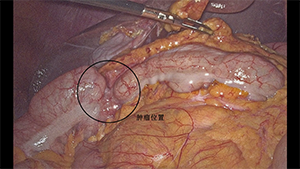

腹部无辅助切口经直肠拖出标本的腹腔镜乙状结肠癌根治术(NOSES)

作者:刘正 | 作者单位:中国医学科学院肿瘤医院

发布时间:2020-09-04 14:03:33